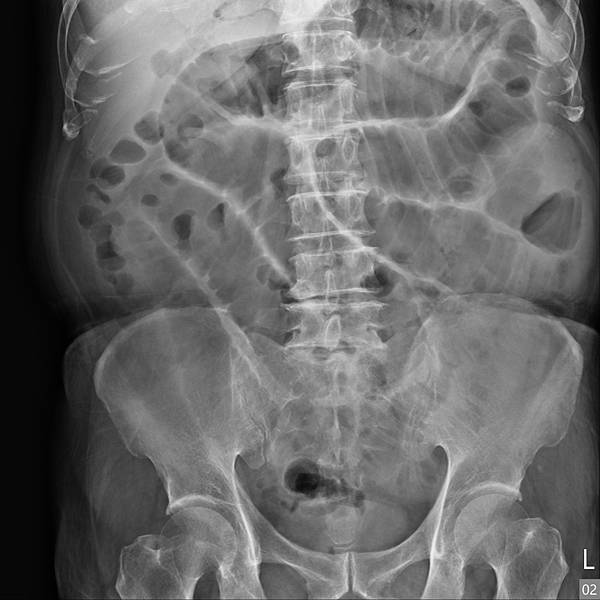

腸躁症有許多種病因,是一種大腸鏡看起來正常的慢性大腸發炎。長期便秘、腹瀉、腹脹、腹痛,不管病人陳述甚麼症狀,KUB絕對不能省掉,之前照過你還是要再照一次。CBC-DC與CRP也不能省,不時會有驚人的發現。